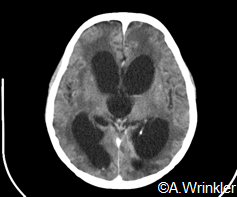

The normal life cycle entails a human final host with the adult tapeworm (taeniasis) and a pig intermediate host with the metacestode larval stage (cysticercosis). People get infected by the consumption of undercooked infected pork. Pigs get infected by the consumption of infected human stool with tapeworm eggs/proglottids. Unfortunately, people can also act as dead end intermediate host, after ingestion of tapeworm eggs via fecal-oral contamination, whereby the larval stages have a tendency to settle in the human central nervous system (Murrell, 2005). The latter condition, neurocysticercosis (NCC) is responsible of about 30% of acquired epilepsy cases in endemic areas (Ndimubanzi et al., 2010).

The parasite occurs primarily in developing countries, where conditions of poverty, low sanitation and free-range pig keeping prevail, and meat inspection is mostly absent. Prevalence of active cysticercosis infection of 20% in humans and over 60% in pigs have been described (Coral-Almeida et al., 2015). CT scan studies in highly endemic areas estimated that over half of the acquired epilepsy cases in those areas were due to NCC, indicating the urgent need for control (Mwape et al., 2015).